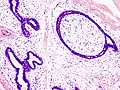

| Histopathologic image of breast fibroadenoma. Core needle biopsy. H&E stain. | |

Fibroadenoma of the breast is a benign tumor composed of a biplastic proliferation of both stromal and epithelial components.[12][13] This biplasia can be arranged in two growth patterns: pericanalicular (stromal proliferation around epithelial structures) and intracanalicular (stromal proliferation compressing the epithelial structures into slit-like spaces).

These tumors characteristically display hypovascular stroma compared to malignant neoplasms.[2][14][9] Furthermore, the epithelial proliferation appears in a single terminal ductal unit and describes duct-like spaces surrounded by a fibroblastic stroma. The basement membrane is intact.[15]

Fibroadenoma histology (H&E). The image demonstrates intracanalicular morphology (bottom left) and pericanalicular morphology (top right)